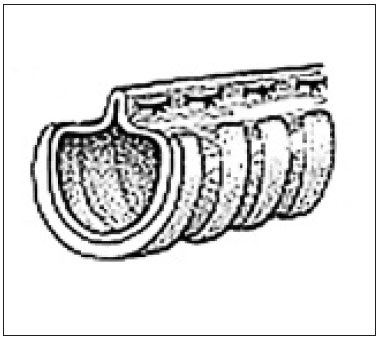

Alkalmazási technikáinak redők dorsalis tracheális membránjával betegek egy kis fokú összeomlása a légcső, amikor porcos gyűrűk megtartják alakjukat és dorsalis membrán feleslegben (1. és 2. fokozat). Bemetszést ejtenek mentén középvonalon, felfedve a nyaki légcső, majd folytatja sternotomiaból metszést bevonása esetén mellkasi légcsövet elválasztjuk. Széles gyengült tracheális membrán összevarrtuk csomózott öltések (menet - monofil nem felszívódó). Ez megakadályozza behajlást eredményez a membránon keresztül a lumen a légcső és a légúti elzáródás. Súlyos trachea porcgyűrű trachea összeomlása és lelapul dorsoventrally alkotják fele a kerülete a légcső. Ezzel kapcsolatban a technika alkalmazása során a redők dorsalis membrán nem ajánlott, mert okozhat súlyos szűkülete a lumen. Amikor a 3.-4. fok az összeomlás, amikor a szélessége a dorzális a membrán felületével felével egyenlő a kerülete a légcső, körülbelül 25% -a a kerülete a meglévő berendezések során elvész a gyűrődések kialakulása. Potenciális keresztmetszeti területe a légcső csökken mintegy 44% (A. Wendell Nelson betegségei a légcső és bronch) (ábra8).

A külső rögzítőszerkezet légcsőgyűrűket alkalmazásával elválasztottuk polipropilén. Ezek készülhetnek fecskendőhengeréhez vagy lehet az ipari termelés. Műanyag gyűrű körülveszi a légcső részlegesen lefedő azt 2/3, az szükséges, hogy a rugalmasság és a lehetőségeket, hogy mozgassa a légcső során lélegzik. Fontos, hogy a beültetés a gyűrűk nem volt zavaró a vérellátása és beidegzése a légcső. Használata gyűrűk különböző átmérőjű, a belső átmérője van kiválasztva átmérőjétől függően a légcső. Külső stabilizáció, nézetünk szerint kell használni nyaki összeomlás és közelebbi mellkasi összeomlása miatt beállítás a külső része az implantátum a mellkas rendkívül nehéz megvalósítani, nem komolyan megzavarják a funkció a vérellátása és beidegzése (9. ábra).

Operatív keresztül elérhető egy középvonali hasi bemetszést a garat a mellkasi belépő. Támasztógyürü egymás felett helyezkednek dorsoventral oldalán a légcső. A gyűrűk kapcsolódnak a légcső útján ízületek 5, amelyek egymáson vannak, mindegyik gyűrűn. Erre a célra az egyes támasztógyűrű előzőleg kifúrt öt nyílások: egy nyílás mindkét végén gyűrű, egy mindkét oldalán oldalirányban és dorsalis membrán. Varratokat alkalmaznak monofil szállal nem felszívódó (5-0), a további szövet varrt rétegekben (10. ábra).